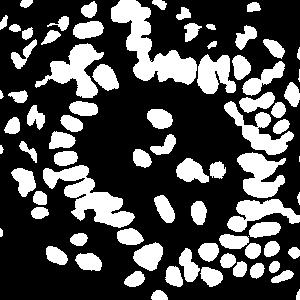

(a) image

(b) round 1

(c) round 2

(d) round 3

An example is shown in Fig. 2 to illustrate the masks in different rounds of self-training. The foreground nuclei annotation (green pixels) is kept unchanged during the iterations while the background area (pixels in black) grows up gradually. In the third round, the background has high accuracy and the ignored pixels (orange) are almost all nuclei.